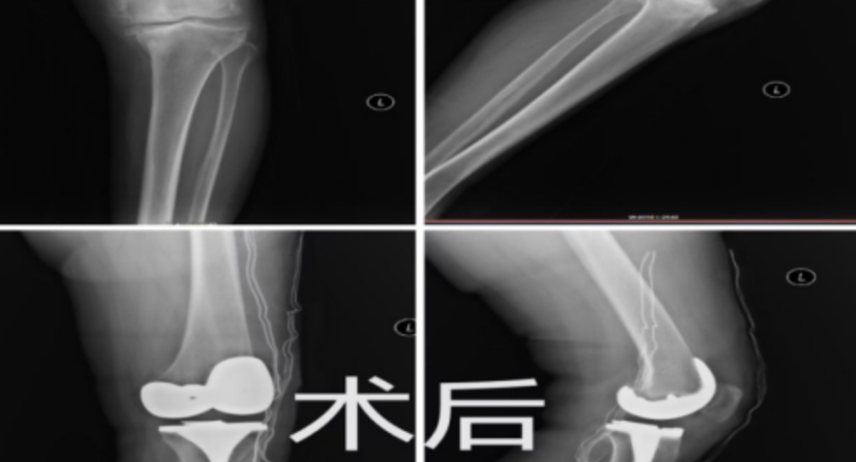

以旧换新,告别“躺平”!膝关节置换术为68岁老人重塑新“膝”望

健康

膝关节

湖南医聊

2024-12-09